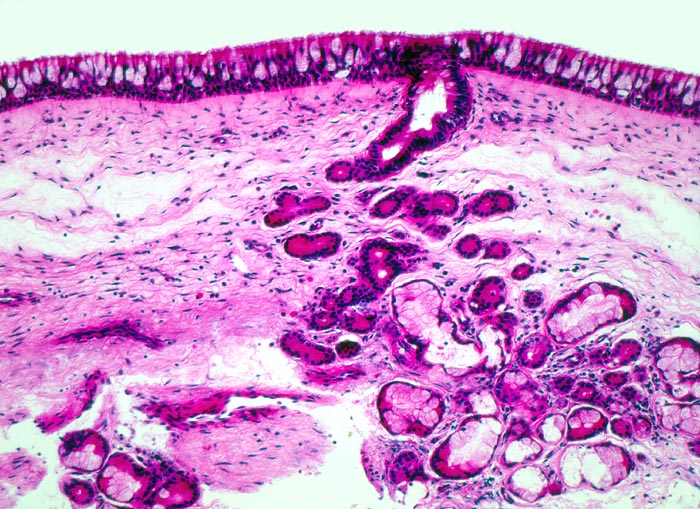

• Polypoides Gewebsfragment bedeckt von mehrreihigem Flimmerepithel.

• Im Zentrum des Polypen Drüsenläppchen und zahlreiche Blutgefässe.